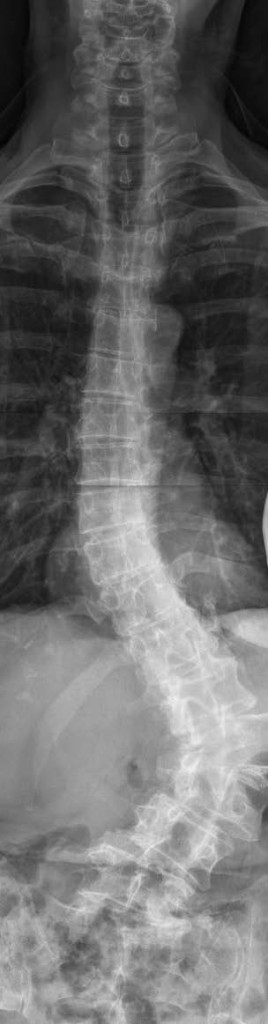

In the past 12 years, my scoliosis had advanced from a stable 26 degree curve to a curve over 70 degrees, and the curve was continuing to progress. I am 65 years old and since many of my family members have lived into their 90s, I knew I would be severely compromised if I lived as long. I decided to come to HSS and discuss my options and the pros and cons of surgery with Dr. Han Jo Kim.

After talking with Dr. Kim, I became convinced that surgery was my best option, and Dr. Kim performed my spinal fusion surgery in late 2014. It has truly changed the course of my life. My spine has been straightened to a remarkable degree, and I am 1 ½ inches taller. I am in physical therapy now and discovering my increased abilities. Without surgery, I would have faced a life of increasingly severe restrictions due to my scoliosis.